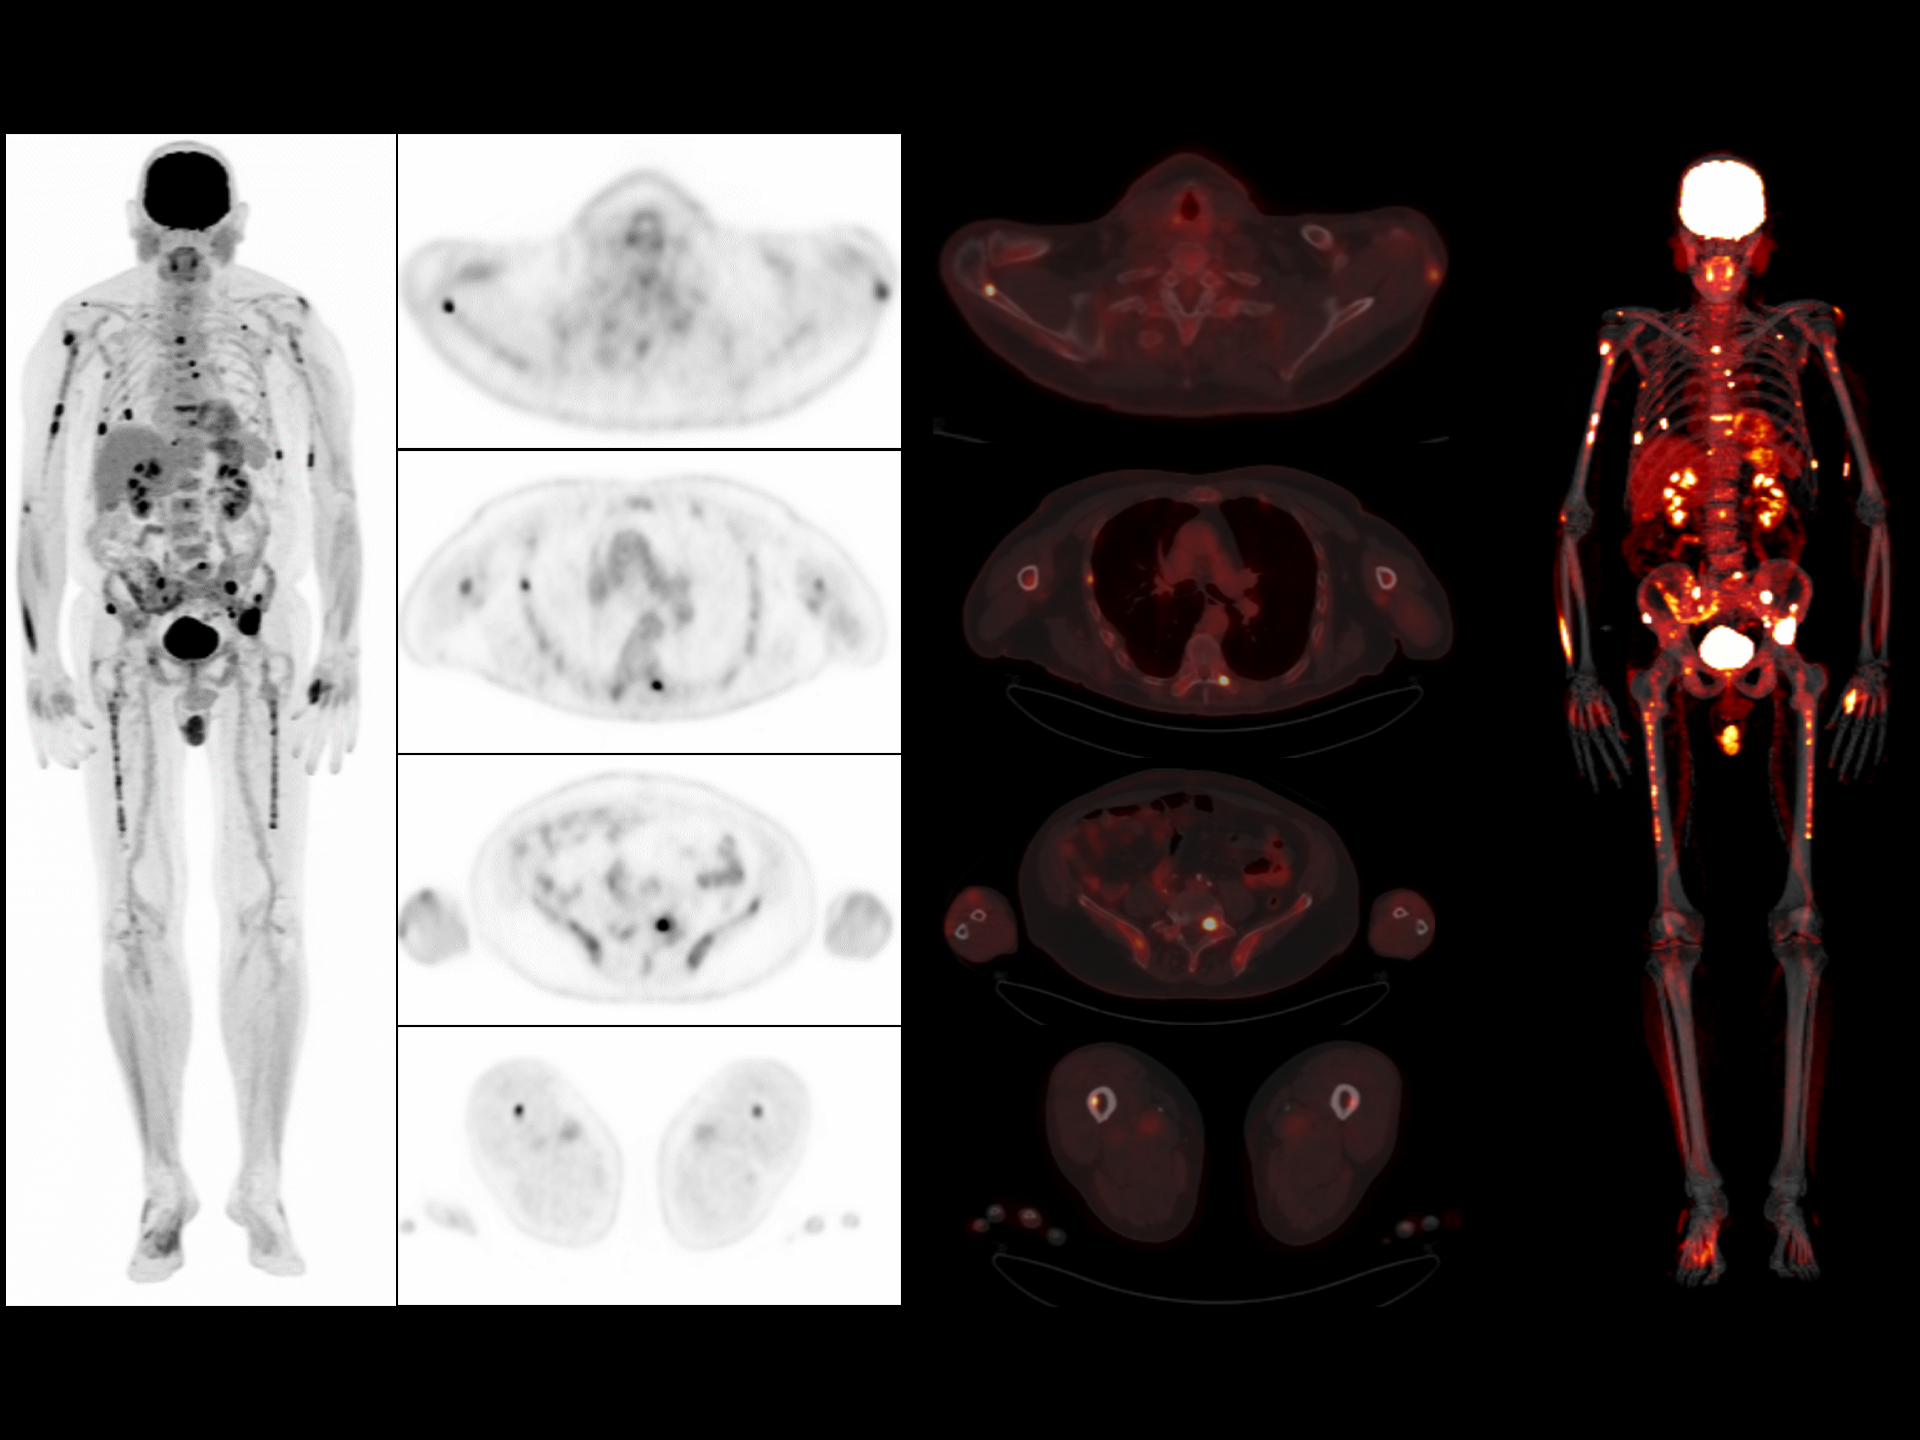

Clarity enhanced by ultra-fast Time of Flight (TOF) resolution of 219 ps enabling better lesion detectability and quantitative accuracy*

*Images Courtesy of Pueblo Medical Imaging